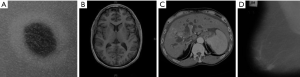

Therefore, the low bound and the high bound in this problem for the algorithm are selected as [LB, UB]=[0, 2]. Here, the termination criterion is reached if the best solution stays the same for 10 iterations. Figure 4 shows the images which were analyzed in this study for illustrating the efficiency of the system in comparison to different state-of-the-art methods. As can be see, we utilized different kinds of cancers to show the generality of the proposed system.

The optimal values of Gamma for medical images, including skin cancer, brain tumor, liver cancer, and breast cancer, are illustrated in Table 3.

Figure 8 shows the results of the methods for the liver tumor. Looking at the figure, it is clear that BPDFHE and BBHE have insufficient results for this case study, as their histograms are shifted to the right-hand side and left-hand side, respectively. PSO has comparatively better results for the image than the two methods above, but the proposed method, GAPSO, and the CLAHE, have the most suitable results for this case, with the histogram of the presented method and the CLAHE method being superior to GAPSO for image thresholding purposes.

The final result concerns breast cancer processing. As is evident from Figure 9, BPDFHE is the worst method this case, while PSO’s results are not satisfactory. In addition, the histogram of the BBHE has low brightness, and is consequently not very suitable for image processing applications. PSO, GAPSO, and the CLAHE nearly have better results for the subsequent image processing steps, but as can be seen, the results of the presented method are considerably appealing.